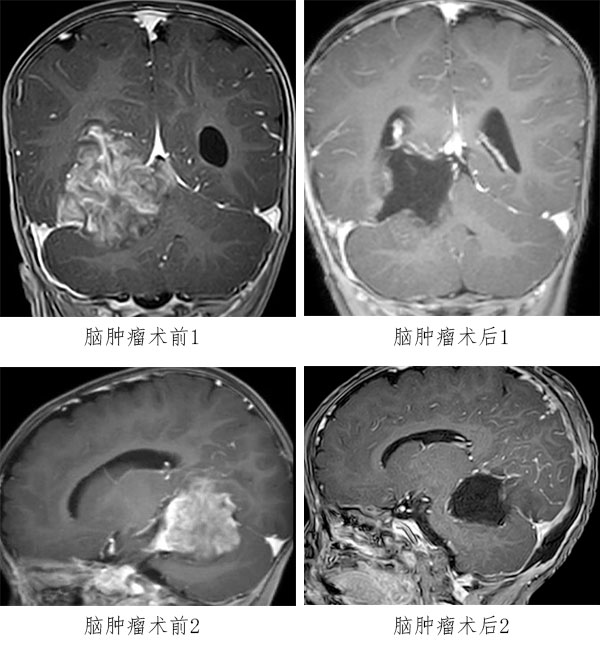

入院后,患儿头颅MRI平扫+增强提示:右侧小脑幕上下骑跨巨大肿瘤,压迫右侧丘脑、侧脑室、脑干、小脑等重要结构,考虑胚胎型肿瘤可能性大。肿瘤与周围组织无明显边界,手术难度极大、风险极高。

2026年3月3日,由张玉琪院长主刀,经枕下幕上入路小脑幕上、下病变切除术。手术历时4小时,镜下近全切除肿瘤,周围脑干、颅神经及血管保护良好,出血仅100ml。术后患儿转入NICU(新生儿重症监护病房),次日平稳返回普通病房。病理确诊为胚胎性肿瘤,WHO Ⅳ级(世界卫生组织(WHO)根据肿瘤恶性程度划分的最高级别(IV级)的恶性肿瘤)。术后虽康复情况充满挑战,但由医护团队通过中西医结合治疗后顺利恢复健康,并于术后第17天顺利启动第一周期化疗。